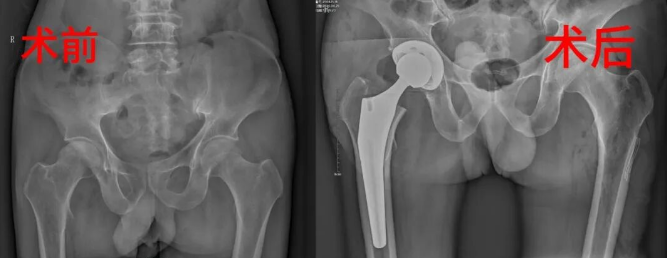

患者因双髋关节疼痛三年到骨伤科就诊,确诊为双侧股骨头缺血性坏死。科室采用"分步治疗"方案——先通过机器人辅助完成右侧人工全髋关节置换术,术中利用切除的健康股骨头制备自体骨颗粒;随后运用天玑骨科手术机器人三维定位系统,在左侧股骨头建立植骨通道,将自体骨精准植入坏死区域,有效清除病灶并重建血运。

股骨头坏死作为致残率高的骨科疑难病症,传统治疗面临定位难、创伤大等问题。天玑手术机器人通过智能规划,可精准避开重要血管神经,实现微创化治疗。该技术不仅能有效延缓病情进展,更为患者争取了宝贵的自体骨移植机会,显著降低假体置换带来的并发症风险及经济负担。